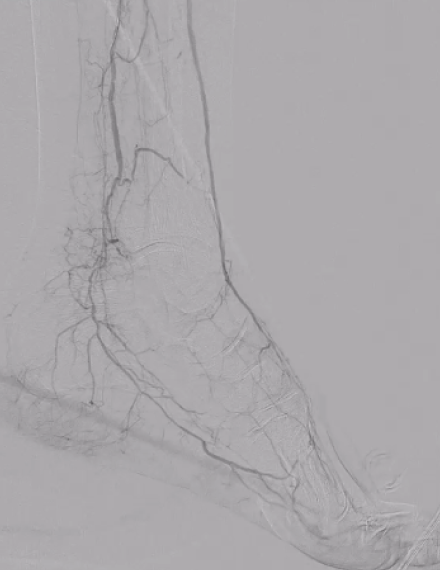

Post-procedure

Final angio shows restored flow of the anterior tibial artery. ABI post procedure: 0.75. -

Foot angio shows direct flow from the anterior tibial artery into the dorsalis pedis and increased perfusion to the heel.